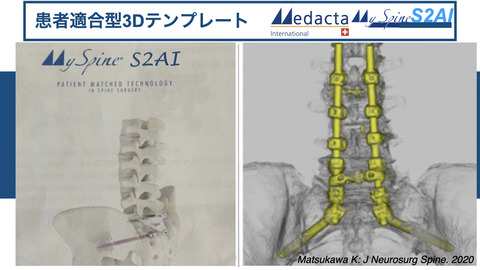

2020年8月17日に「祝!!MySpineS2AIが薬事承認」の記事を投稿しました。

ぜったい便利、超絶便利だと思います、とかなりの期待を寄せておりました。

実際に使用する機会を得ましたので、報告いたします。

ガイドの作成のために大事だと感じたことを自分なりにまとめます。

①S1は外から内に向かう軌道でテンプレートを作成すると、どうしても腸骨で筋肉が外側に展開できず、邪魔になってしまい、ガイドのフィッティングがかなり難しくなってしまうので、sagittalでの軌道はPESにして上に抜き、axialでの軌道は、まっすぐかやや内から外にむかう軌道でテンプレートを作成するほうが良さそうです。

もちろん、S1は血管の存在を十分ケアしてプランニングをたてないといけません。

②あと、ロッドが連結しやすいよう、SAIのヘッドと腰椎スクリュー、S1スクリューのヘッドの位置を一直線になるようにプランニングします。

③そして、S1のヘッドとSAIのヘッドが干渉しないように、刺入点にゆとりをもたすようにプランニングする、

ということが大事だと思いました。